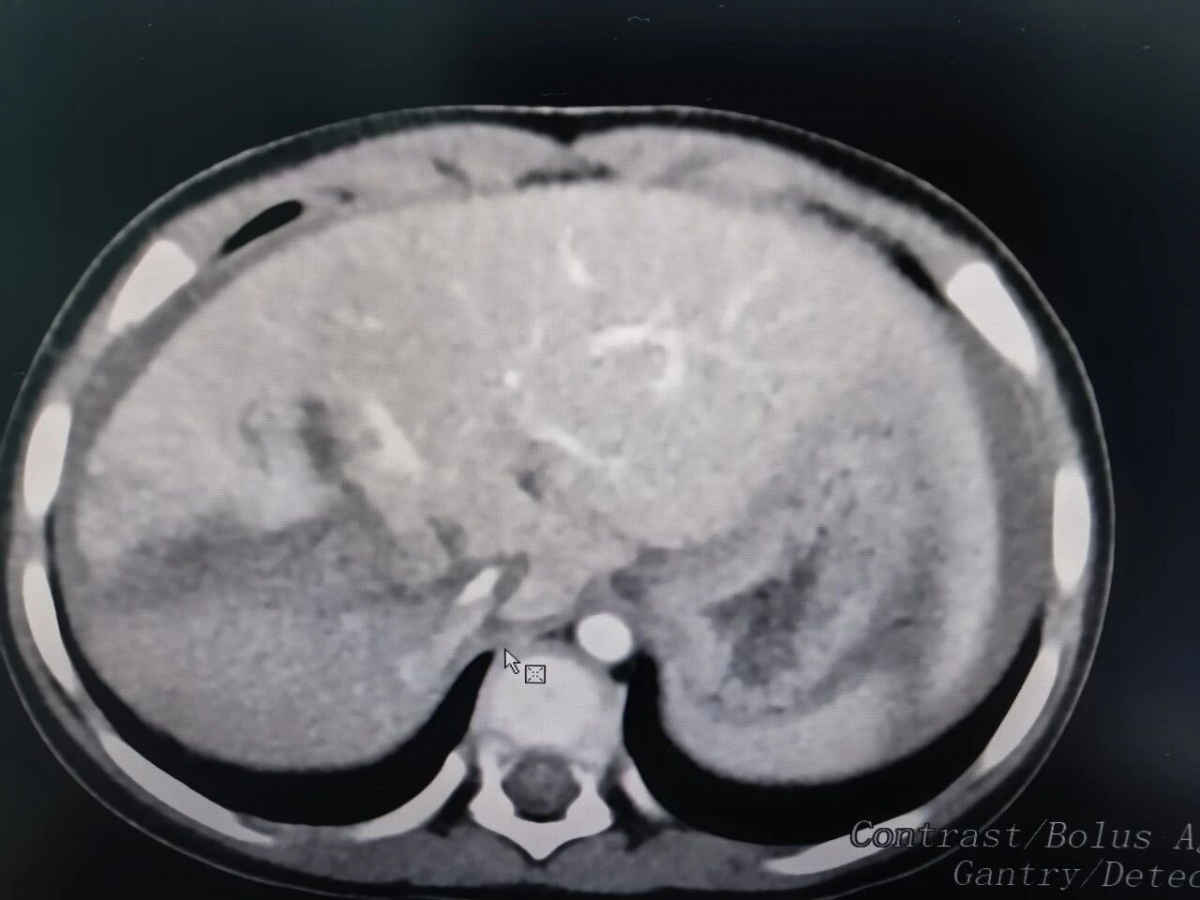

抢救小组再次复盘CT,发现患儿肝脏右后叶完全损毁,血肿范围较大,从第一肝门一直裂至第二肝门。林继宗立即向中山三院岭南医院普通外科主任刘波详实汇报情况,商量手术方案。刘波认为本着损伤控制的原则,采用最快最简单又能解决出血的手术方式,必要时直接切除右后叶。

患儿肝脏毁损状况

在何波迅速完成麻醉后,林继宗组织开展剖腹探查手术,发现患儿右肝后叶表面完全裂伤,如豆腐碎裂,再次修补可能性微乎其微。结合刘波主任提出的专业建议,林继宗决定实施右后叶切除手术。尽管此项手术面临着难度高、风险大等诸多挑战,但这是让患儿能够存活下来的唯一可行方案。